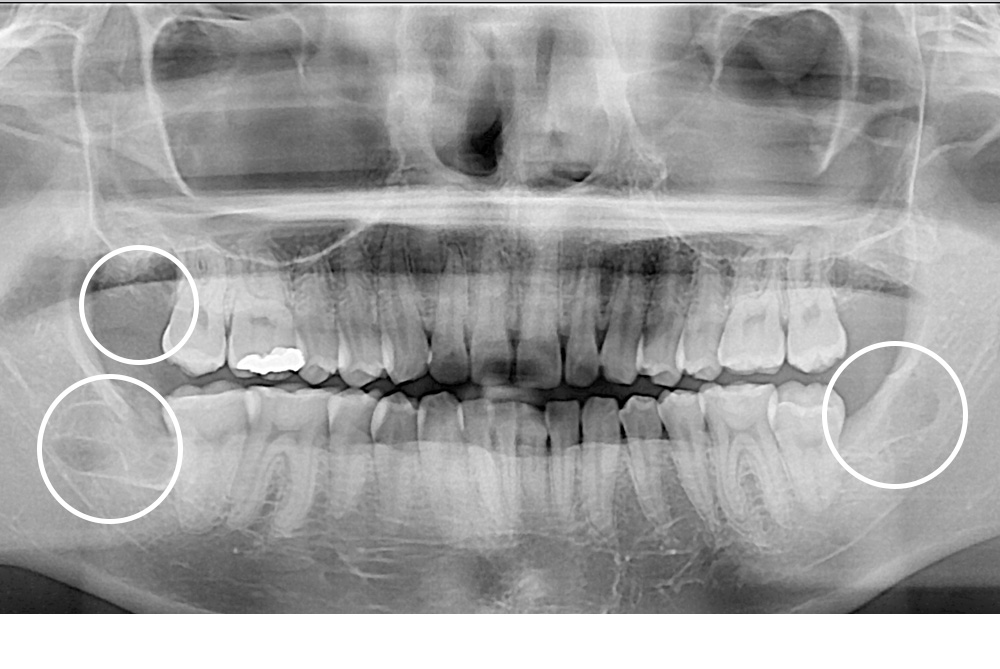

치료후 : 2020-03-16

세종치과는 구강악안면외과학 박사이신 원장님이 발치하는 치과입니다.